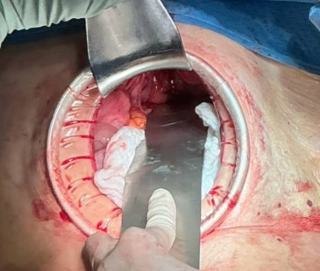

A 31-year-old previously healthy woman, with no surgical history, presented with sudden-onset, severe peri-umbilical abdominal pain unresponsive to high-dose opioids. CT-scan revealed mildly dilated distal jejunum with mesenteric edema and free fluid (Fig. 1, 2). Because of persistent pain despite step III analgesia, emergency diagnostic laparoscopy was performed. Intraoperatively, a closed-loop obstruction of an ileal segment was identified, herniated through a narrow internal window formed by an adherent mesenteric vessel supplying a Meckel’s diverticulum (Fig. 3). The vascular band was divided, releasing the closed loop, with no irreversible small bowel ischemic damage. The Meckel’s diverticulum was resected. The post-operative course was uneventful, and the patient was discharged after two days.